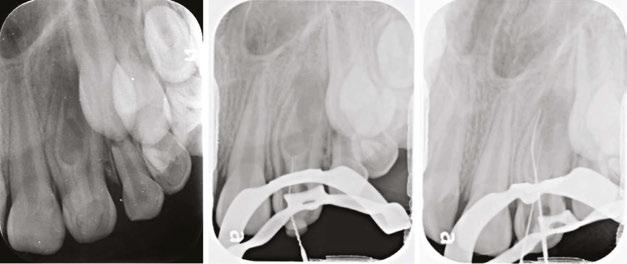

int the C-shaped main canal. 3D.The obturated enamel of lined canals with Biodentine. The radiopacity is similar to that of dentin. 3E. Healing of the periapical lesion in the 3-year follow-up and continued root formation

Figures 3A-3E: 3A Periapical radiograph of the dens in dente. It is impossible to determine the accurate source of infection. 3B. Hedstrom file in the invagination. 3C. Files

An 8.5-year-old girl was referred by her pediatric dentist due to extraoral swelling that extended into the infra-orbital space originating from the left lateral incisor. The immature tooth had only 2/3 of the root completed and therefore was staged as Nolla 8.10 The deciduous lateral incisor was extracted at the age of 2 years after a traumatic dental injury. She was administered Amoxycillin to manage the infection.

Considering the irregular anatomy of the tooth, which was seen in the periapical radiograph, the patient was referred

for a small-field CBCT scan. A Class III dens invaginatus was verified. A few days after undergoing emergency treatment, including incision and drainage at the oral surgery department, swelling in the buccal vestibule was still evident upon arrival at the follow-up appointment. Local anesthesia was administered before tooth isolation with a rubber dam. Access cavity was then achieved through the invagination alone, and a transpar-

ent liquid leaked from the canal. The invagination was then irrigated with 3% NaOCl and 17% EDTA, dressed with CaOH2, and sealed with a temporary filling material (Coltosol), placed between appointments. Ten days later, at a follow-up appointment, there was still buccal swelling, so similar irrigation and dressing were repeated.

Two weeks later, since there was still swelling, it was decided to treat the main canal as well. The main canal was prepared and irrigated with copious irrigation with 3% NaOCl and 17% EDTA, combined with the use of SAF (Redent Nova, Raanana, Israel) owing to its ability to adapt three-dimensionally to the shape of the canal, and its continuous flow of irrigant through its hollow file, which facilitates better cleaning and debridement. Dressing of the invagination and the main canal were done with a slurry of calcium hydroxide (Ca(OH)2). This step led to the resolution of the swelling; therefore, at the next appointment, it was decided to obturate the canals with Biodentine® (Septodont), and the access cavity was filled with a composite resin.

Follow-up examinations were scheduled for 6 months and then yearly. At the 3-year follow-up, complete healing was observed; continuous PDL was observed around the root and resolution of the periapical lesion. The immature root canals continued to develop, and apical closure is evident in the periapical radiograph.